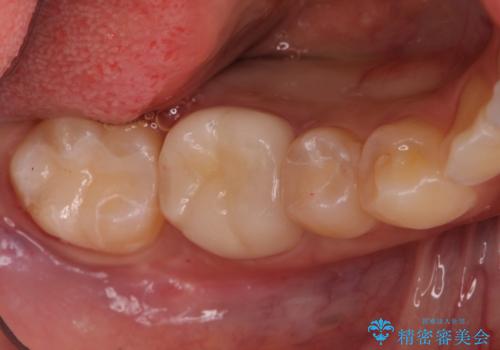

- 右下の保険治療での樹脂の劣化、および歯と歯の間の虫歯をセラミックのつめもので治療しました。

右下6番はセラミックのアンレーが入っていましたが、強度の問題もあり、やり直し後はクラウンとしました。